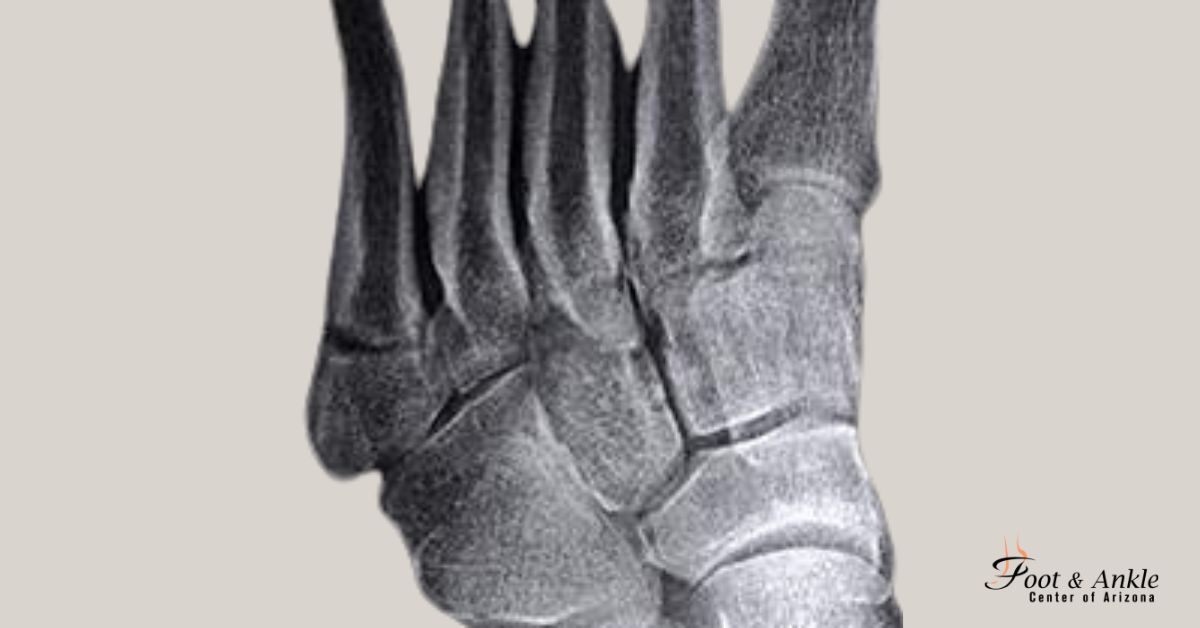

- X-rays: Provide detailed insight into the degree of misalignment.

- Include a video or sample X-ray image to illustrate how bunions appear.